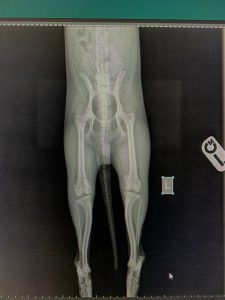

- Liječenje prijeloma kostiju, uključujući intraartikularne frakture

- Liječenje luksacije patele(Luxatio Patellae) Trohleoplastika i TTT(eng. Tibial Tuberosity Transposition)

- Korektivne osteotomije za ispravljanje deformiteta

- Liječenje rupture prednjeg križnog ligamenta koljena TPLO (eng. Tibial Plateau Leveling Osteotomy)